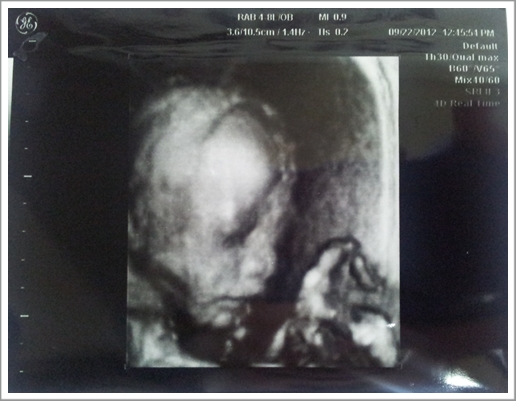

這天照超音波和4D超音波一切都很正常

24週寶寶的體重大約是500~800克重,妹妹則是775克

最後產檢結束前,妹妹也終於讓我們看到她的小臉

然後醫師說了句:『妹妹看起來很秀氣喔!很棒呢~~』